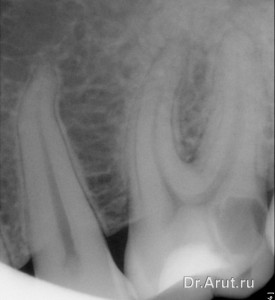

Несколько лет спустя после лечения пациентка обратилась в нашу стоматологическую клинику с жалобами на постоянные ноющие боли в 46. Изучив анамнез заболевания и проведя осмотр пациентки был установлен диагноз обострение хронического пульпита.

Лечение: трепанация зуба через пломбу, вскрытие полости зуба, ампутация и экстирпация пульпы, инструментальная и медикаментозная обработка корневых каналов. Каналы запломбированы гуттаперчевыми штифтами с AH plus методом вертикальной конденсации. Коронковая часть зуба восстановлена композиционным пломбировочным материалом.

- Глубокий кариес

- Обострение хронического пульпита